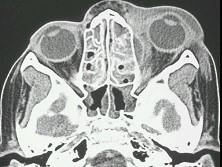

问题 眼眶蜂窝织炎(如图)的严重并发症有 ( )

选项 A、败血症 B、眼球萎缩 C、视神经萎缩 D、化脓性脑膜炎 E、海绵窦血栓形成

答案 ACDE